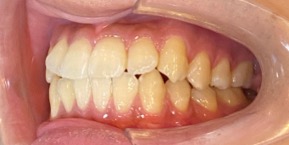

26歳女性のビフォーアフター

| 診断 | 空隙,叢生 |

| 治療方針 | 治療方針:前歯の咬合関係改善と空隙閉鎖を主な目的にて主にIPR(歯と歯の間をわずかに削合してスペースを獲得する方法)を組み込んだ動的矯正治療を行い、空隙、前歯咬合を改善後、保定を行う。臼歯部の咬合関係はプランの都合上維持することとした |

| 治療費 ※ | 69万8千円(診断、型取り、矯正中のメンテナンス、保定装置を含む料金) |

| 治療期間 | 1年8か月 |